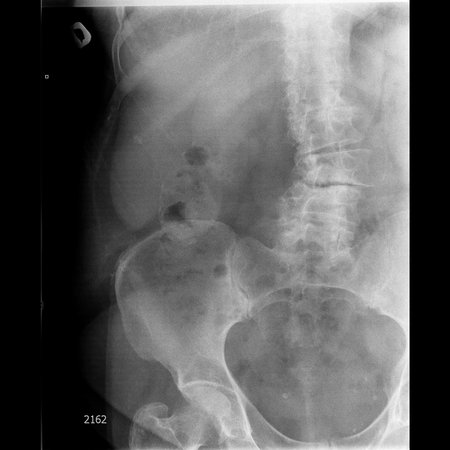

Фарфоровый желчный пузырь (Porcelain gallbladder)

Женщина средних лет без жалоб на здоровье.

Еще случай.

Бабушка из отделения сестринского ухода, без жалоб на боли в животе. Лаб. анализы не изменены.

Если кальциноз стенки полный и содержимое пузыря осмотру не доступно, то есть показания к проведению КТ-МРТ. Если стенки инкрустированы частично (как в представленных случаях) и можно оценить характер содержимого и структуру стенок, то можно ограничиться только УЗИ. Далее, если есть подозрение на опухоль то пациента направляют к онкологу, а он сам определяет дальнейшую тактику.

Это форма хронического холецистита с кальцификацией стенки ЖП. Термин "фарфоровый" отражает голубоватый оттенок и хрупкую консистенцию ЖП. У мужчин возникает в 5 раз чаще. Кальцификация стенки представляет собой либо непрерывную кальцификацию мышечного слоя, либо прерывистую кальцификацию слизистой и подслизистой. У таких больных высока частота возникновения рака ЖП (11-33%) Каждый раз, когда при УЗИ имеется подозрение на фарфоровый ЖП, для подтверждения диагноза и оценки степени злокачественности проводят КТ